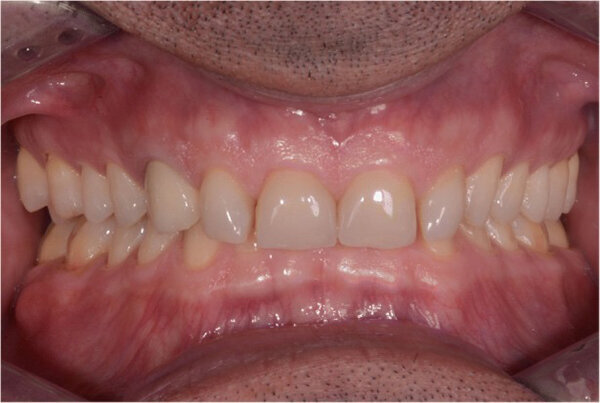

El paciente regresó a la clínica en 2017 para reanudar el tratamiento (Fig.7), y se realizó un nuevo escape intraoral (Carestream 3600). Se imprimió un nuevo modelo para la preparación del diente en una impresora 3D (SolFlex, VOCO) con bisacryl (Structur 3) utilizando una matriz compuesta al vacío (V-Print ortho, VOCO). Los pilares de los dientes se prepararon mínimamente sobre la base de la maqueta (Fig. 8).

Fig.7. Dos años después, antes del tratamiento (2017).